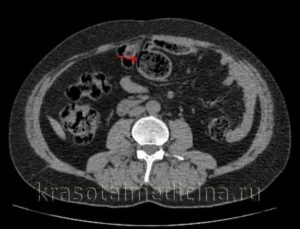

Подтвердить диагноз могут только методы эндоскопии – при них визуально видно газовые пузырьки по ходу кишки.

Могут быть также использованы методы рентгенологической диагностики с контрастом или без него.

Диагностика включает исследование полости кишечника (эндоскопические методы), состояние органов эпигастрии (узи, рентген с контрастированием), анализы мочи, крови и кала.

Узи органов брюшной полости